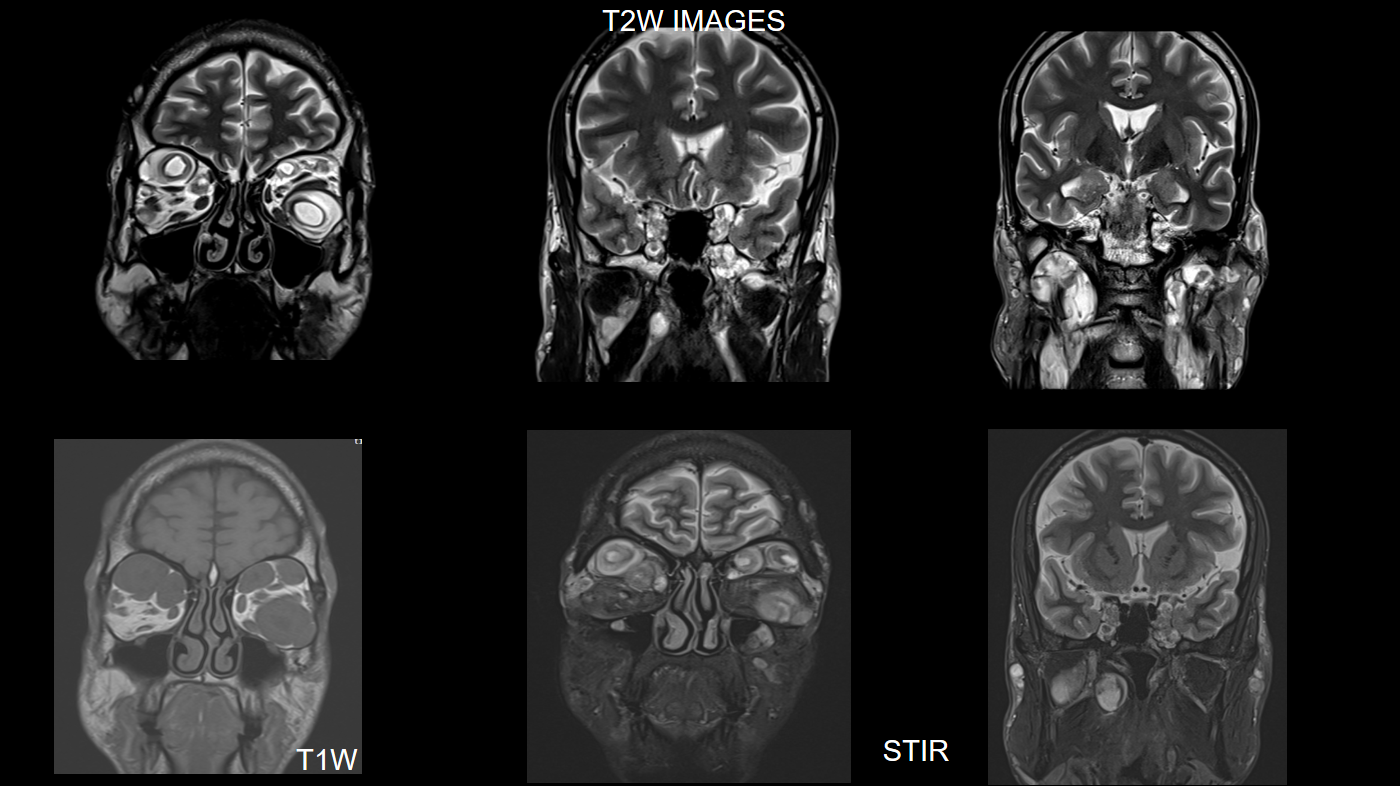

FINDINGS – MRI BRAIN WITH IV CONTRAST

Multinodular T2 hyperintense hypointense transpatial lesions seen within the bilateral orbits occupying the intra and extraconal spaces with targetoid appearance.

The lesion extends through the inferior orbital fissure into the pterygopalatine fossa bilaterally.

The lesions also extend through the foramen ovale into the superior aspect of masticator space bilaterally.

Similar heterogeneously enhancing nodular lesions are also seen bilateral fronto-temporal and occipital scalp regions. Incidental retrocerebellar arachnoid cyst.

Lesion extends into the orbital apex and along the bilateral cavernous sinuses.

Similar heterogeneously enhancing nodular lesions are seen extending into the upper neck in bilateral parotid and the visualised level II regions.

The lesions show heterogenous post-contrast enhancement.

Extensive orbitofacial plexiform neurofibroma.

They are best visualised on fat suppressed T2 weighted MR imaging where they appear as hyperintense masses with or without multiple target signs.

They demonstrate mild enhancement with IV gadolinium and are isointense on T1 signal.